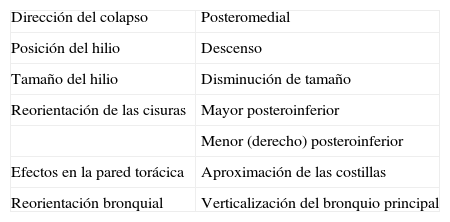

La atelectasia pulmonar es un indicador importante de una enfermedad subyacente, potencialmente grave, que es imprescindible diagnosticar precozmente. Uno de los mecanismos más frecuentes es la reabsorción de aire distal a la obstrucción de las vías respiratorias. La radiografía de tórax es una herramienta excelente para diagnosticarla, especialmente útil para descartar obstrucciones bronquiales centrales (por ejemplo, una neoplasia endobronquial). Si no se reconocen correctamente los signos de la pérdida de volumen el diagnóstico y el tratamiento pueden retrasarse. En este artículo se describen los principales hallazgos radiográficos de la atelectasia pulmonar lobular y su correlación con la tomografía computarizada. Se incluyen los signos clásicos descritos en la bibliografía y otros menos conocidos y a su vez sutiles.

Atelectasis is an important indicator of potentially severe underlying disease that must be diagnosed as early as possible. One of the most common mechanisms is the reabsorption of air distal to respiratory tract obstruction. The chest X-ray is an excellent tool to diagnose atelectasis, and it is especially useful for ruling out central bronchial obstructions (e.g., from endobronchial tumors). If the signs of volume loss are not recognized correctly, the diagnosis and treatment can be delayed. This article describes the main findings of lobar atelectasis on chest X-rays and their correlations with CT findings, including the classic signs described in the literature and other, less known and sometimes subtle signs.